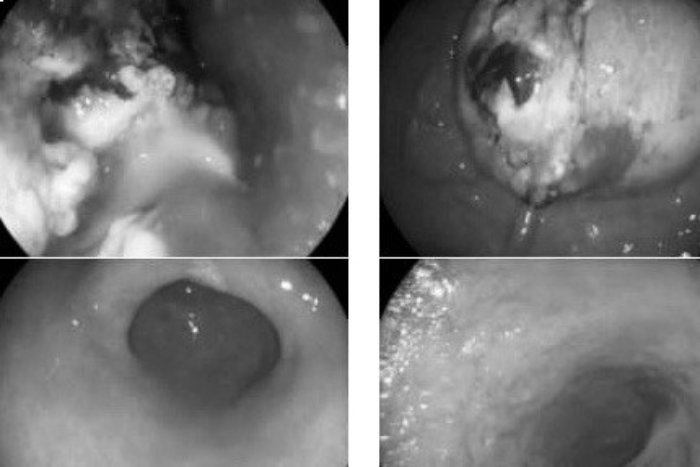

Lần thứ 3 đến khám, bác sĩ Thành cho biết bệnh nhân gầy sút cân nhiều, ăn uống khó khăn, gần như không thể ăn được thức ăn đặc, cơ thể ốm yếu. Khi nội soi, các bác sĩ thấy khối u đã to lên chiếm gần hết lòng thực quản, dây soi qua khó khăn. Các hạch cũng tiếp tục phát triển. Dạ dày bệnh nhân cũng có vết loét. U dạ dày đã được sinh thiết và cùng nguồn gốc với u thực quản.